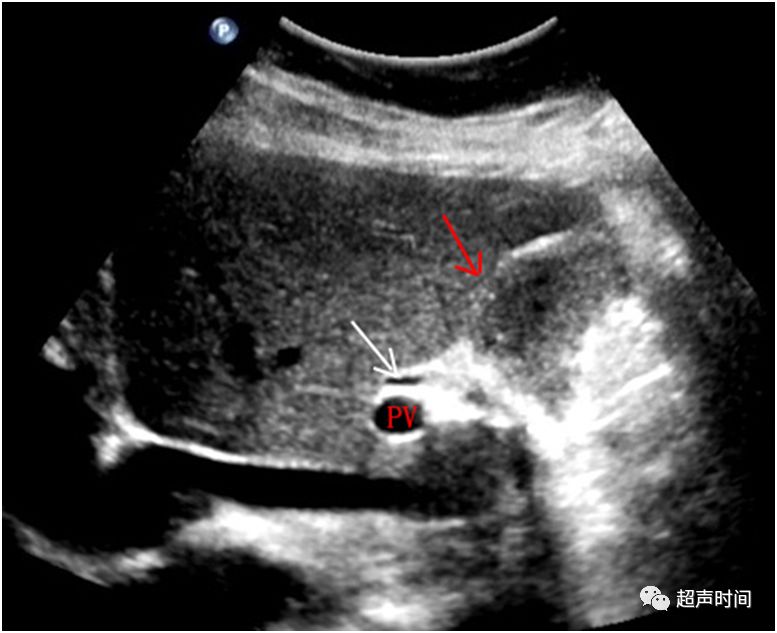

术后 1 月患者空腹行门诊超声复查,发现胆囊窝处探及疑似「胆囊」轮廓(图 2),肝门处胆管轻度扩张(图 3)。在多次核对患者信息及查看患者住院病历后请上级医师会诊,嘱患者食两个油煎鸡蛋 30 分钟后再次检查,发现胆囊窝处未见异常,肝门处胆管未见扩张(图 4)。

图 2 胆囊窝处探及「胆囊」轮廓,疑似「胆囊」

图 3 肝门处胆管轻度扩张,管壁光滑,管壁内回声清晰(白色箭头)。PV:门静脉